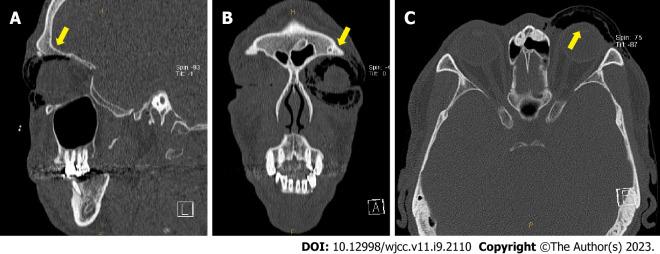

Herein, we describe a case of postoperative subcutaneous emphysema that was treated using a simple needle aspiration method. A 48-year-old male patient visited the hospital with a blow-out fracture of the left medial orbital wall and nasal bone fracture. One day postoperatively, swelling and crepitus in the left periorbital area were observed, and follow-up computed tomography showed emphysema in the left periorbital subcutaneous area. Needle aspiration using an 18-gauge needle and syringe was used to relieve the emphysema. The symptoms of sudden swelling improved immediately, and no recurrence was observed.

在此,我们描述一例使用简单针吸法治疗的术后皮下气肿病例。一名48岁男性患者因左眶内侧壁爆裂性骨折和鼻骨骨折入院。术后一天,观察到左眶周区域肿胀并有捻发音,后续计算机断层扫描显示左眶周皮下区域存在肺气肿。使用18号针头和注射器进行针吸以缓解肺气肿。突然肿胀的症状立即得到改善,且未观察到复发。